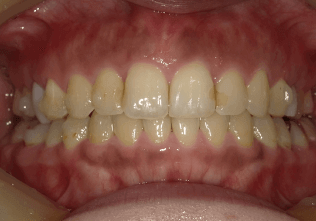

叢生(後戻り)

BEFORE

AFTER

担当医コメント

以前、一度矯正治療を受けたが後戻りにより歯並びに問題が出てきた。上下顎に叢生があり、上顎前歯が前突している。叢生量を鑑みてインビザラインでの治療が可能と判断した

治療の概要

年齢/性別

33歳 女性

主訴

前歯が出ているのが気になる。

一度矯正治療をしたがまた悪くなってしまったので綺麗に治したいでした。

リスク

歯肉退縮が起こる可能性がある。

費用

85万円

期間

10ヶ月

術前

術中

術後